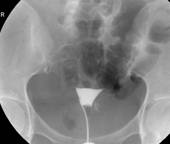

时××,女,39岁,因“阴道不规则出血1月”入院,妇查示:宫颈占位,约5×5cm大小,病理检查示:宫颈部鳞癌。予介入手术,双侧子宫动脉化疗药物灌注,并以明胶海绵颗粒栓塞。3周后行子宫切除术,术后病理:宫颈部瘤体1×1cm大小,淋巴结无转移。